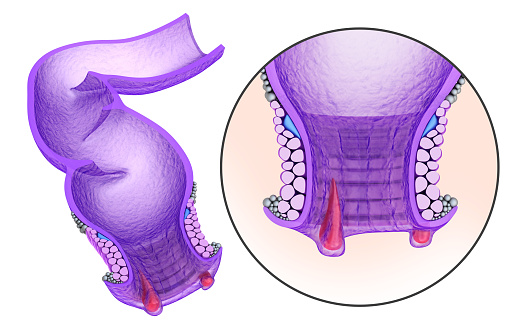

Talk to anyone you know and they’ll probably have some complaint about their digestion. Whether it’s bloating, an upset stomach, or heartburn, it seems that everyone’s suffering. With a rise in digestive woes, there’s a lot of information that’s circling, but unfortunately, not all of it is true. Below you will find some common digestive ...click here to read more